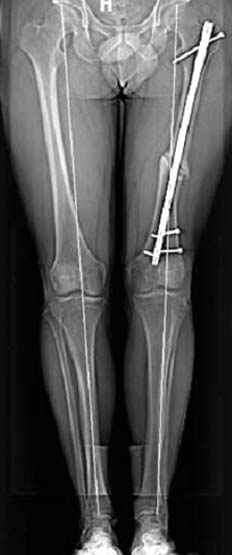

Интересно бы посмотреть рентгенограмму таза (оба сустава) а также рентгенгорамму с захватом коленных суставов (по Dror Paley).

пластическая модель; и коррекция бедра аппаратом Илизарова.